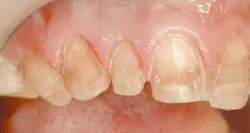

A patient came to my office (fig. 1) with some legitimate esthetic concerns. She had feldspathic porcelain veneers done 16 years ago in an effort to cover dark tetracycline staining. The patient reported being very satisfied with the outcome at the time. However, as time passed, the smile she once felt so good about began to make her feel self-conscious again.

Upon anesthetizing the patient, I decided to remove the old veneers to observe the underlying teeth. I was able to observe the old preparations and the actual color of the teeth. This information will help me with my new preparations (Fig. 6).

We found some severely tetracycline-stained teeth that had hardly any preparation. The result was thick teeth (Fig. 7). This is the main reason the ceramist was not able to correct many of the nuances of the smile design we discussed earlier. Adequate preparation is the only way to obtain a fantastic result.